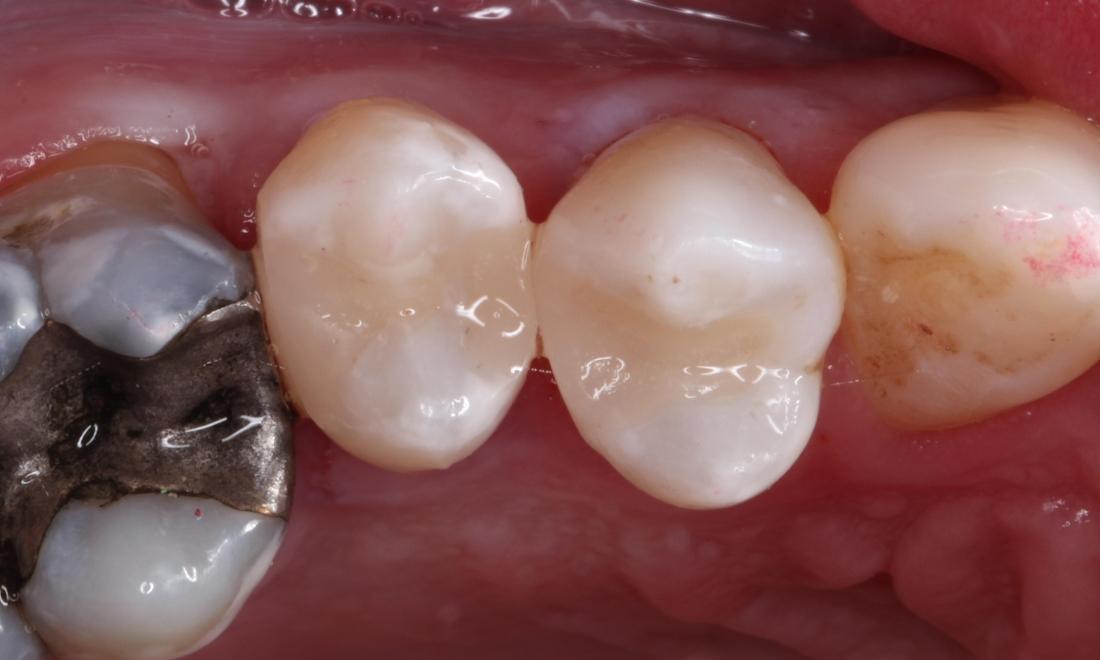

Then we removed the decay and existing filling. The decay and silver caused stain to the inside of the teeth. The teeth were then disinfected and restored to normal color and function with direct composite resin.

Great home care and routine preventative checkups can help this fillings last for many years.